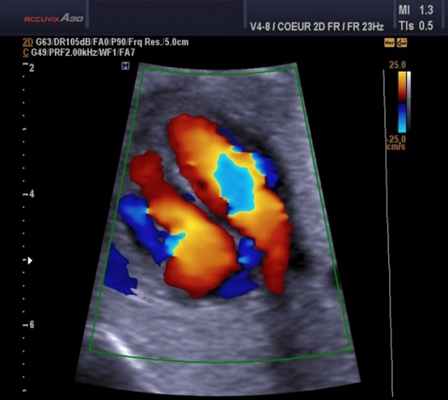

Цветовое допплеровское картирование является разновидностью ИВ допплерографии, при которой кровоток или движение миокарда изображаются разными цветами (обычно красным, синим и зеленым) или их комбинацией, что зависит от скорости, направления и наличия турбулентности.

В каждом участке изображения частотный сдвиг измеряется, преобразуется в цифровой формат, автоматически сопоставляется с заданной цветовой схемой (автокорреляция) и выводится на экран на фоне двухмерного изображения. При оценке кровотока в полостях сердца поток, направленный к датчику и имеющий положительный частотный сдвиг, кодируется оттенками красного. Кровоток, направленный от датчика и имеющий отрицательный частотный сдвиг, колируется оттенками синего.

Оценки в пределах каждого первичного цвета задаются высокими скоростями, не достигающими предела Nyquist. Когда скорость становится выше этого предела, появляется искажение цвета. Турбулентность отражает степень отклонения скоростей в определенной области от средней скорости и кодируется обычно оттенками зеленого.

В связи с этим аномальный кровоток легко распознать по комбинации многочисленных цветов, соответствующих направлениям, скоростям и степени турбулентности. Ширину и размер аномального внутриполостного кровотока используют для оценки степени регургитации на клапанах или выявления впутрисердечных шунтов.

Почти все структурные и гемодинамические сердечные аномалии нарушают кровоток и, следовательно, приводят к изменениям при цветовом допплеровском картировании. Его также используют для определения диастолической дисфункции и длительности фаз сердечного цикла. На рисунке продемонстрированы динамические изменения клапанной регургитации и гемодинамики, записанные с помощью допплерографии и цветового допплера.

Для облегчения выявления турбулентного движения (завихрений) существует порог скорости, выше которого происходит изменение цвета (во многих аппаратах это зелены). «Мозаичный» узор на участке турбулентного потока позволяет легко установить регургитацию (смену направления движения), что помогает определить степень недостаточности клапанов.